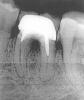

VSedakov Опубликовано 8 сентября, 2007 Поделиться Опубликовано 8 сентября, 2007 (изменено) Первый раз каналы зуба были пролечены 15 лет назад (в детстве). Стояла обширная пломба, которую время от времени подновляли. Сейчас поставили коронку, хотя предлагали зуб удалить, т.к. на снимке, между корней, была видна область воспаления. Коронка вышла чудесной, зуб не болит и все бы хорошо, но с наружной стороны десны как раз посередине зуба появилась опухоль (видимо гранулема) размером 5-7 мм., которая не болит, не кровоточит, но психологически очень мешает. Два раза ее срезали, но она вновь появлялась в первозданном виде. Врач говорит - решайте сами, мол могу ваш зуб и удалить, а могу и дальше срезать вашу опухоль. По ее словам воспаление в области этого зуба между корней - законсервировалось и находится в таком состоянии уже много лет и вряд ли что-то изменится. Также сказала, что если будут малейшие симптомы боли - то надо сразу же зуб удалять. Что делать ? Снимок прилагается ! Изменено 8 сентября, 2007 пользователем VSedakov Ссылка на комментарий

Doc Опубликовано 11 сентября, 2007 Поделиться Опубликовано 11 сентября, 2007 Коронарорадикулярная сепарация. Предложите хирургу, как вариант. Если не выйдет, то тогда удаление и имплантация. Да ну, бросьте! Уж на что я любитель экспериментов, даже могу тоннельную сепарацию показать, но тут ловить нечего. Каналы незапломбированы напрочь, бифуркация никакая, а главное - кариес медиального корня, доходящий до уровня кости. Каждая из этих бед по отдельности уже достаточное основание для сомнений в целесообразности возни, а все три вместе просто перевешивают. Ну что там резать?! Удалять его и имплант ставить! Ссылка на комментарий